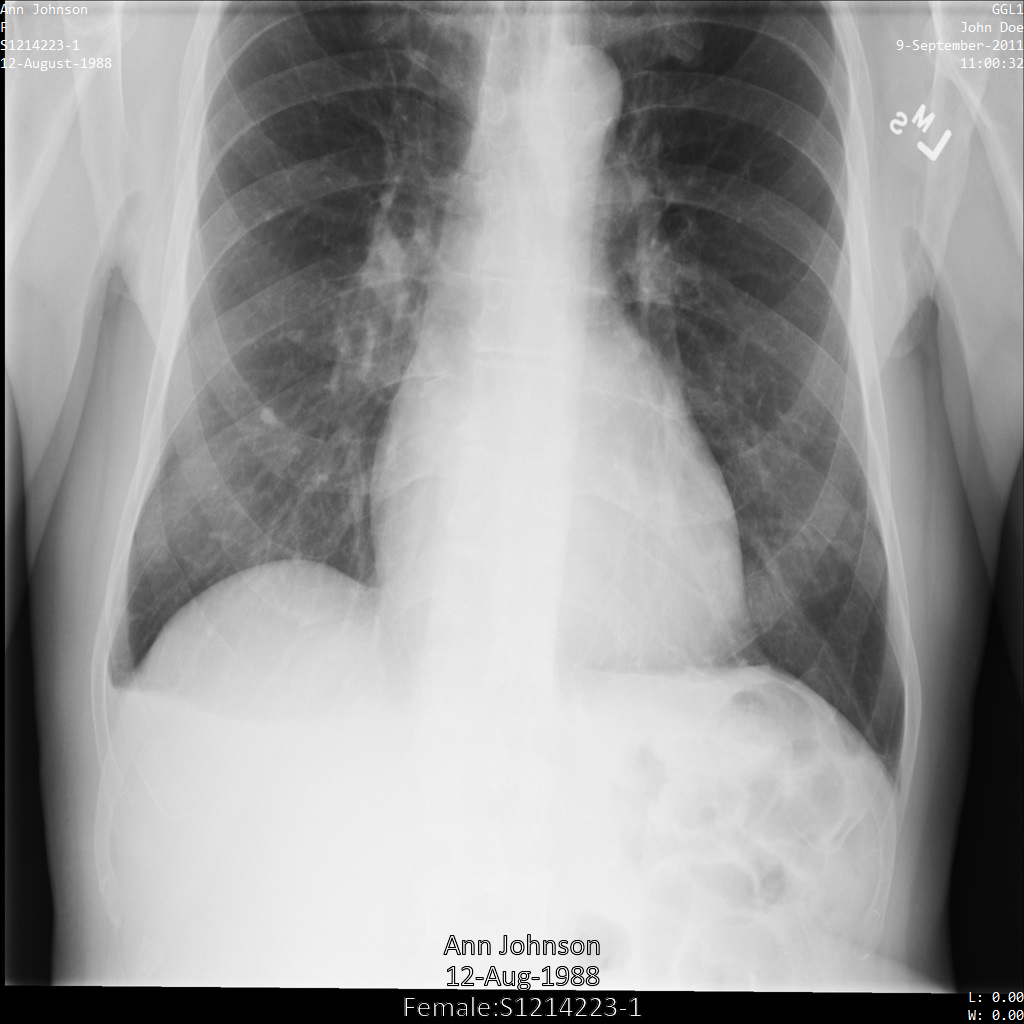

Exemple d'image

Certains exemples de cette page contiennent une sortie de l'image anonymisée. Chaque exemple utilise l'image d'origine suivante comme entrée. Vous pouvez comparer l'image de sortie de chaque opération d'anonymisation à cette image d'origine pour voir les effets de l'opération :